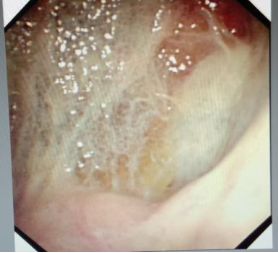

蜘蛛网胸水(包裹性胸腔积液),在胸腔镜下是什么鬼样子的呢?

且看胸腔镜:

胸腔里面这么多分隔,你能保证你的针在哪个小分隔里面?除非你有孙悟空的火眼金睛!

在胸腔镜下,是“蜘蛛网+蜂窝状”般的变态存在。